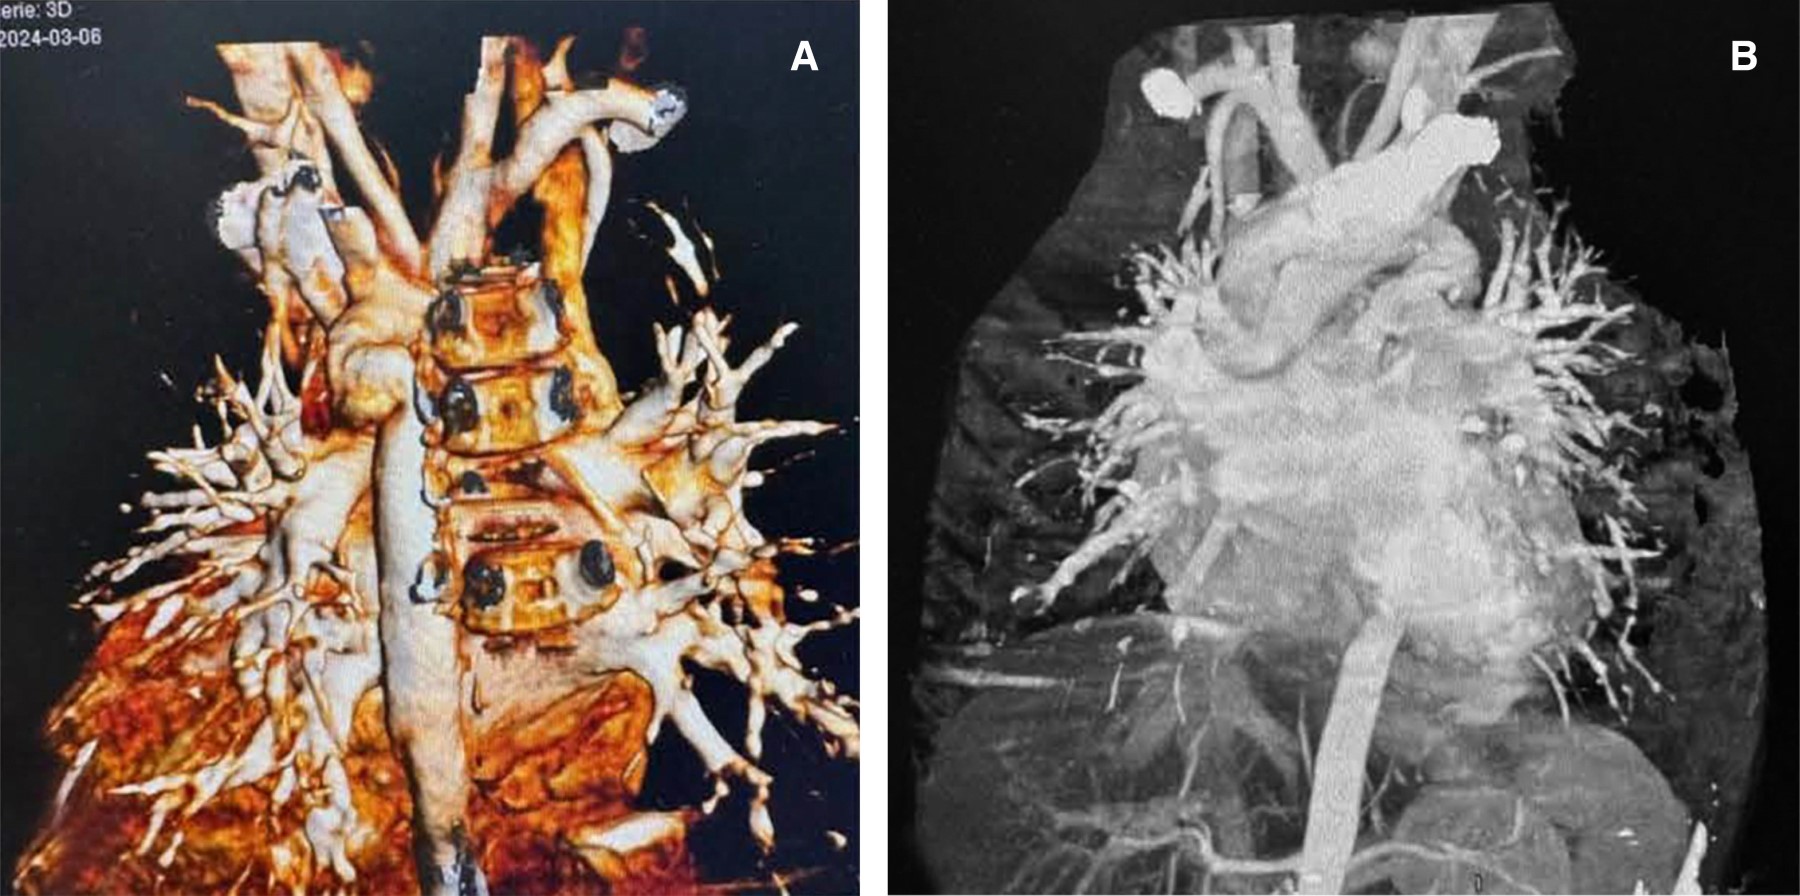

La pseudocoartación aórtica, una anomalía aórtica congénita poco frecuente, simula una coartación, pero generalmente carece de impacto hemodinámico significativo. Presentamos el caso de un niño de seis años evaluado por hipertensión arterial sistémica. El diagnóstico se realizó mediante ecocardiografía, que reveló coartación preductal y un conducto arterioso persistente ancho, confirmado mediante angiografía cardíaca por TC, que mostró un doble estrechamiento y angulación atípicos. Se realizó con éxito una coartectomía quirúrgica y una ligadura del conducto arterioso persistente mediante toracotomía izquierda. La imagenología avanzada es crucial para diferenciar esta afección.

Figura 1